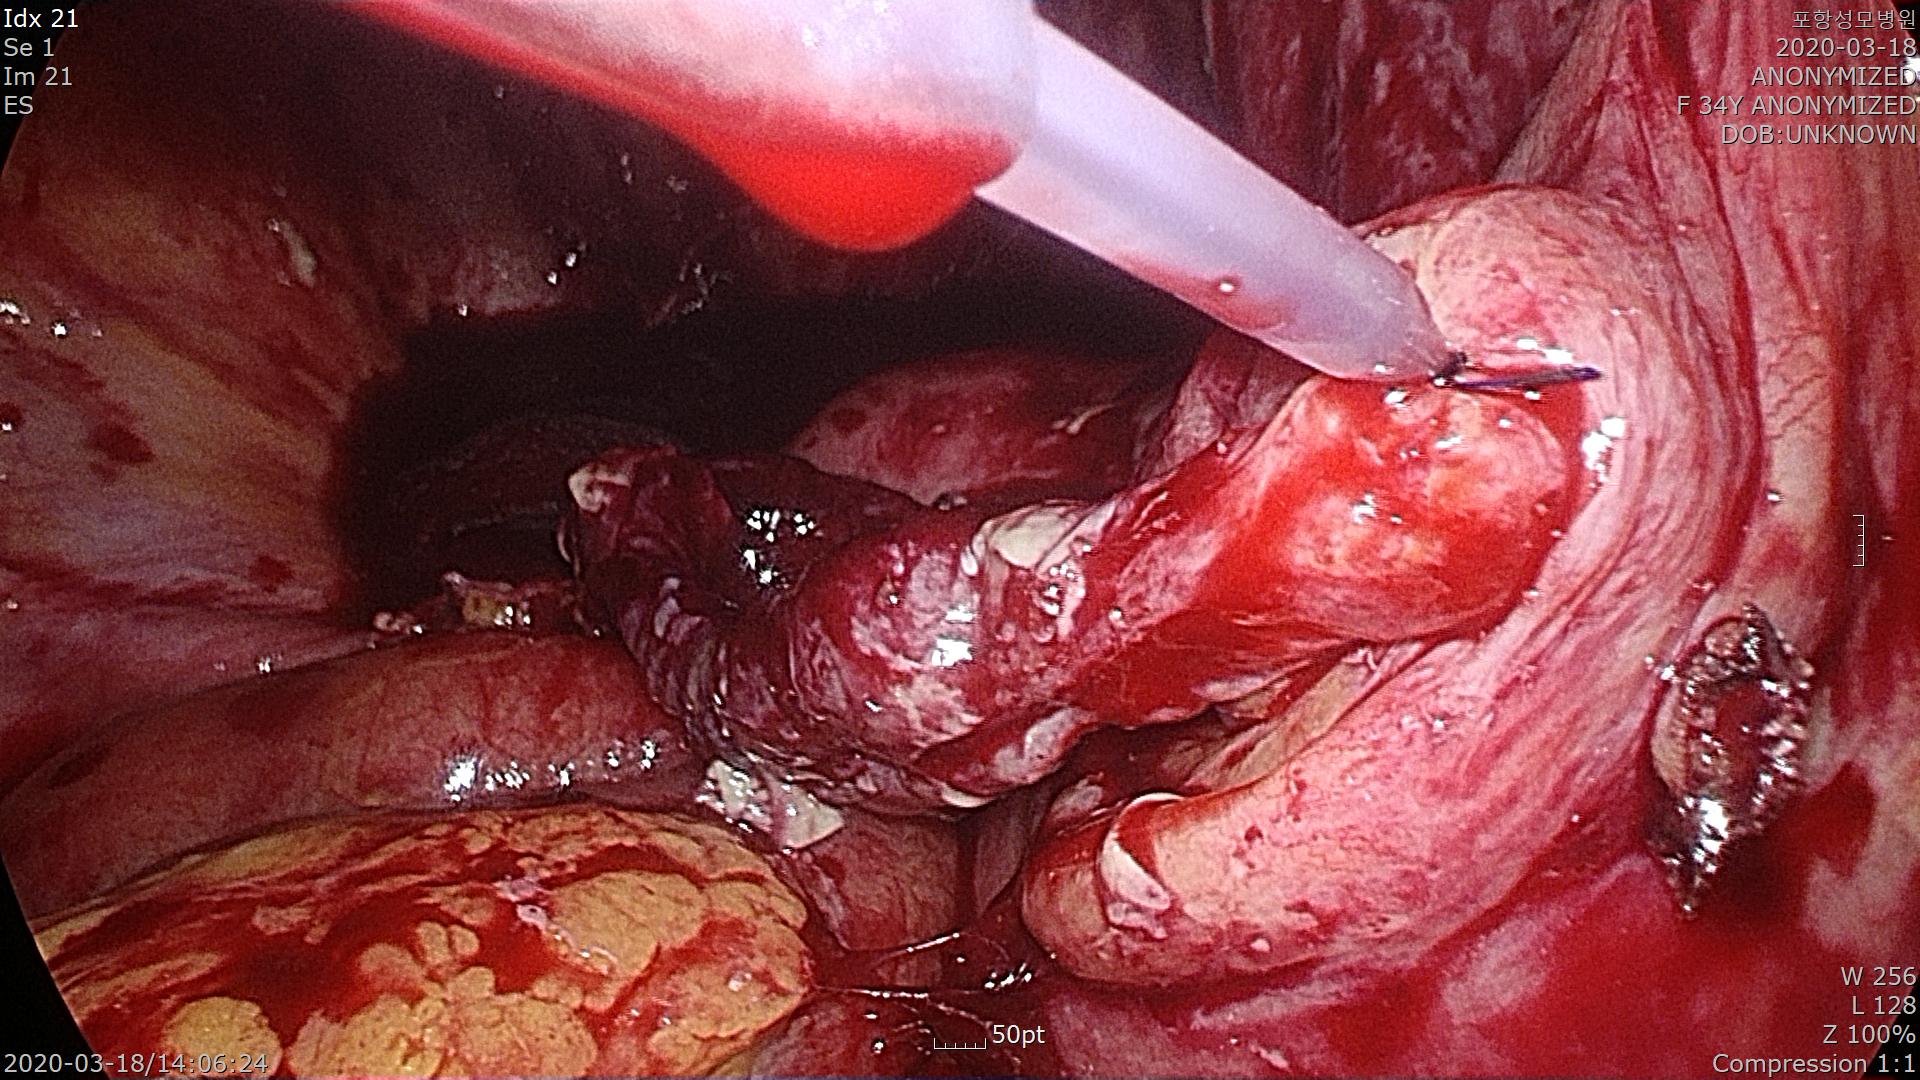

복강내로 접근하자 염증으로 인해 대망(복강내에 있는 큰 지방조직)이 복벽에 유착되어 있습니다.

조심스럽게 떼어냅니다.

충수돌기가 보입니다. 주위에 염증으로 인해 오염된 모습입니다.

소장과 충수돌기가 염증으로 유착되어 조심스럽게 떼어냅니다.